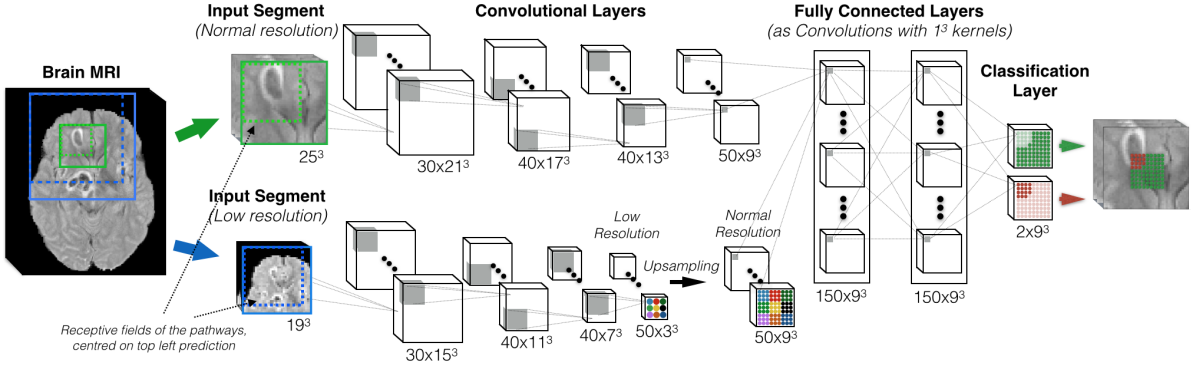

In order to incorporate both local and larger contextual information into our 3D CNN, we add a second pathway that operates on down-sampled images. Thus, our dual pathway 3D CNN simultaneously processes the input image at multiple scales (Fig. 5). Higher level features such as the location within the brain are learned in the second pathway, while the detailed local appearance of structures is captured in the first. As the two pathways are decoupled in this architecture, arbitrarily large context can be processed by the second pathway by simply adjusting the down-sampling factor . The size of the pathways can be independently adjusted according to the computational capacity and the task at hand, which may require relatively more or less filters focused on the down-sampled context.

To preserve the capability of dense inference, spatial correspondence of the activations in the FMs of the last convolutional layers of the two pathways, and , should be ensured. In networks where only unary kernel strides are used, such as the proposed architecture, this requires that for every shifts of the receptive field over the normal resolution input, only one shift is performed by over the down-sampled input. Hence it is required that the dimensions of the FMs in are . From Eq. (2), the size of the input to the second pathway is and similar is the relation between and . These establish the relation between the required dimensions of the input segments from the two resolutions, which can then be extracted centered on the same image location. The FMs of are up-sampled to match the dimensions of ’s FMs and are then concatenated together. We add two more hidden layers for combining the multi-scale features before the final classification, as shown in Fig. 5. Integration of the multi-scale parallel pathways in architectures with non-unary strides is discussed in A.

The final version of the proposed network architecture, referred to as “DeepMedic”, is built by extending the Deep+ model with a second convolutional pathway that is identical to the first one. Two hidden layers are added for combining the multi-scale features before the classification layer, resulting in a deep network of 11-layers (cf. Fig. 5). The input segments to the second pathway are extracted from the images down-sampled by a factor of three. Thus, the network is capable of capturing context in a area of the original image through the receptive field of the lower-resolution pathway, while only doubling the computational and memory requirements over the single pathway CNN. In comparison, the most recent 2D CNN systems proposed for lesion segmentation (Havaei et al. (2015); Pereira et al. (2015)) have a receptive field limited to voxels.